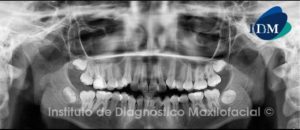

Paciente sexo femenino, 11 años de edad, acude a la consulta para evaluación previo a tratamiento odontológico. Al examen radiográfico panorámico (Fig. 1) observamos múltiples lesiones radiolúcidas que comprometen ambos maxilares.